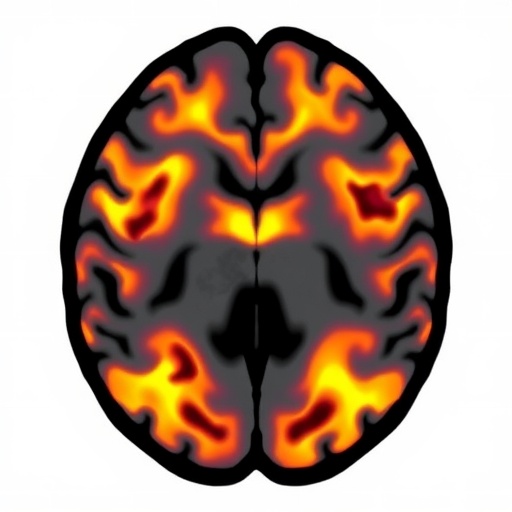

The research team employed advanced neuroimaging techniques alongside meticulous biochemical analyses to map changes occurring in white matter tracts. Vigilant observation revealed that vigabatrin exposure correlates with specific diffusion abnormalities, predominantly within the periventricular white matter regions. These regions, integral for neural connectivity and signal propagation, exhibited signs consistent with intramyelinic edema rather than outright demyelination, a distinction pivotal for understanding reversibility and clinical implications.

Delving deeper, Almudhry and Mir proposed a model implicating vigabatrin-induced osmotic imbalances within myelin sheaths, which could cause myelin swelling. This theory builds on prior understandings but uniquely links elevated GABA levels to disruption of astrocyte function and water homeostasis, culminating in the MRI-visible abnormalities. Specifically, alterations in the astroglial uptake of neurotransmitters and aquaporin channel regulation are suspected to play a vital role in this process, amplifying the intracellular-extracellular fluid shifts that manifest as edematous changes.